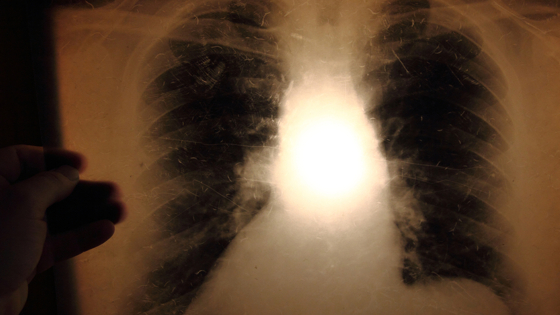

Паразиты повышают восприимчивость к туберкулезу

Американские ученые выяснили, что инфицирование паразитическими червями приводит к повышению восприимчивости к туберкулезу. Это открытие было сделано при наблюдении за лабораторными животными, у которых изгнание паразита вызывало повышение эффективности лечения инфекции микобактериями. Выявленная закономерность объясняет эпидемию туберкулеза в социально неблагополучных странах, где нет доступа к качественной пище и чистой воде. Профилактика гельминтозов при помощи недорогих препаратов может стать мерой профилактики туберкулезной и других тяжелых легочных инфекций.